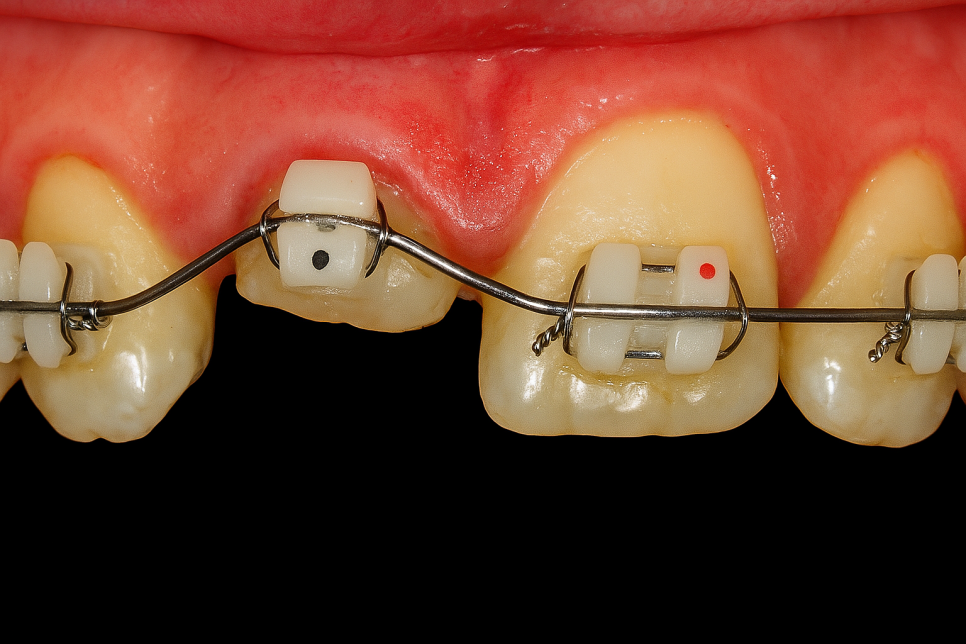

그래서 보철 치료 시 치아 주변으로

2mm 정도의 건강한 자연치 조직을

끌어올려 확보하는 것이 중요합니다.

이를 페룰효.과(Ferrule Effect)라 하는데,

이것이 반영이 되어야 구조의 안정성을

높일 수 있습니다.

때문에 인위적으로 이를 끌어올려 주어야

진료가 가능한데 이것을 정출술이라 합니다.

✅ 교정

브라켓이나 철사 같은 교정 기구를

부착해 서서히 이를 움직이게 해서

잇몸 밖으로 당겨내는 방식을 말합니다.

위 기간에는 임시로 보조 장치나

임시치를 사용할 수 있어 미관이나

평소 생활에 대한 고민을 덜 수도 있답니다.